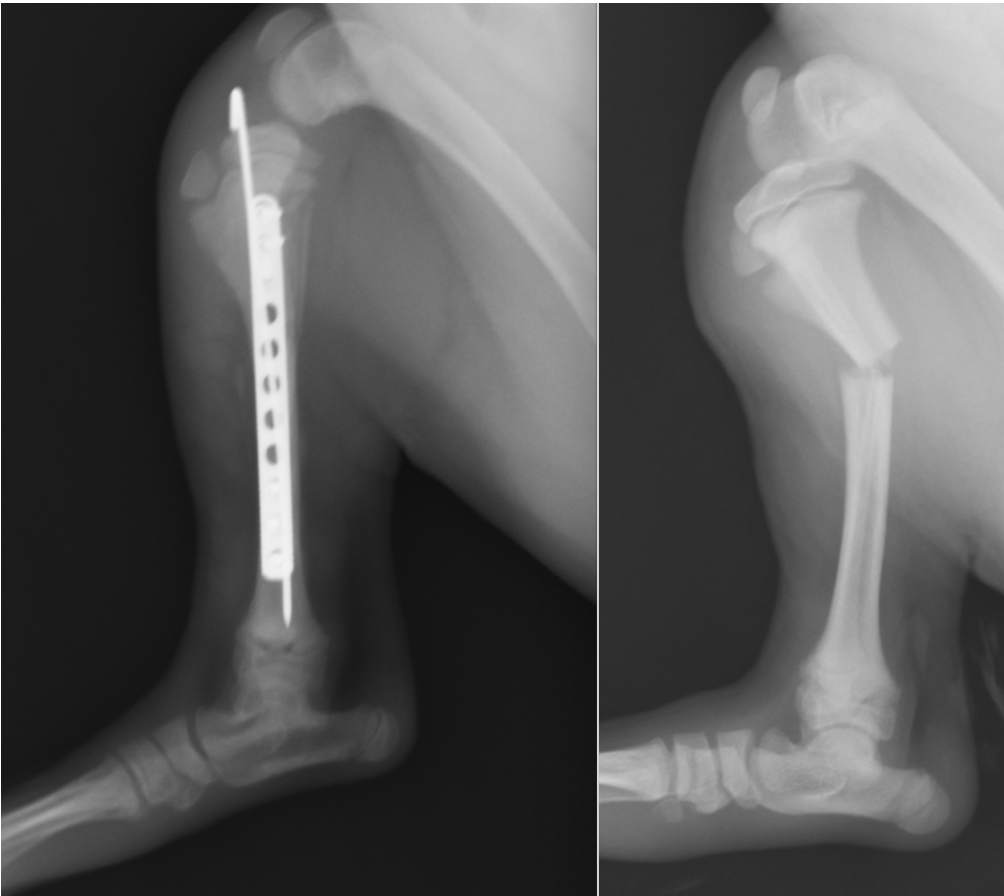

脛骨骨幹部骨折です。この位置は曲げ応力が強くプレート1枚では曲がってしまう可能性があるため髄内ピンをあわせています。この方法をプレートロッド法といいます。

上の症例の正面のレントゲンです。プレートロッド法は脛骨や大腿骨、上腕骨で適用となります。